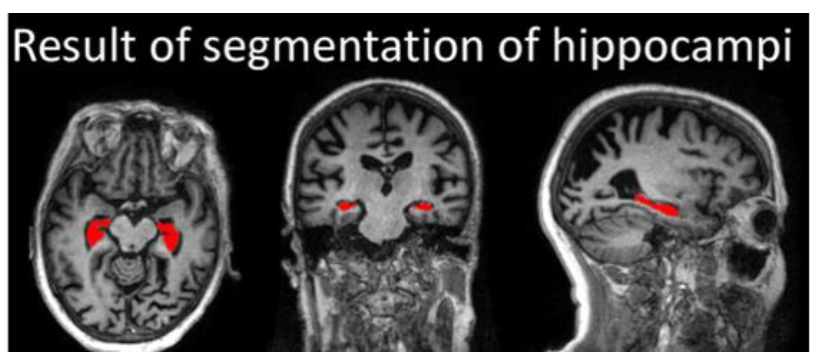

(3) 磁振造影術(MRI):既可直接看到全腦構造(圖四),又可看見阿茲海默症易損部位,如:海馬迴的萎縮及皮質變薄等(圖五)。可同時提供較完整的信息,所以成為目前失智症最重要的篩檢與診斷工具。

(圖五)腦部三種切面,紅色區域即為海馬迴位置。│ NeuroImage: Clinical 11 (2016) 435-49